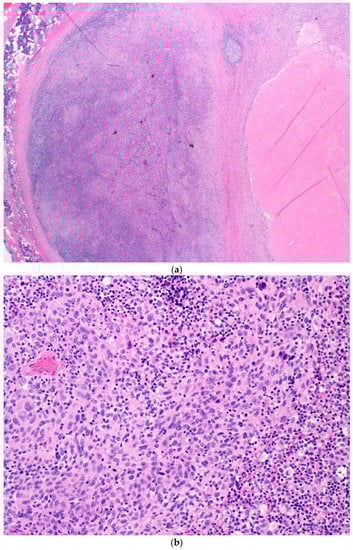

Figure 2 shows images taken from a surgically resected intraparotid LN sample from patient one, demonstrating treatment response and residual viable tumour cells

Figure 2.

(a) A low-power shot at 10× magnification showing the intraparotid LN with areas of tumour necrosis on the right. (b) A high-power shot showing the intraparotid LN with areas of residual viable melanoma. (c) A high-power shot showing the intraparotid LN with areas of fibrosis and tumour necrosis.